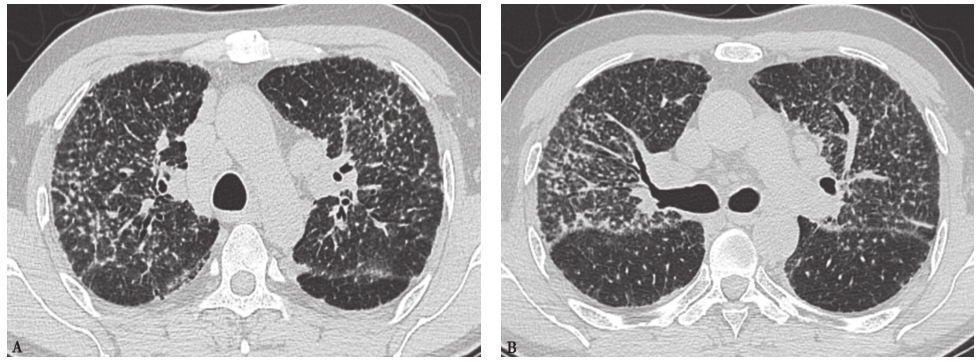

(5)结节病:是一种免疫介导的以非干酪样上皮样细胞肉芽肿为病理特征的多系统性疾病,肺部最常受累,起病隐匿、症状较轻,缺乏特异性,影像学主要表现为双侧肺门、纵隔淋巴结对称性肿大,肺内弥漫性小结节影,沿淋巴道分布,以中心和上肺野为主,晚期患者可有肺间质纤维化、蜂窝肺、囊性支气管扩张等。结节病的典型结节直径为1~5mm,也可大至5~10mm,通常位于支气管血管束周围及胸膜下、叶间裂附近,随着病变进展,可见肺内弥漫性分布呈粟粒样改变,边界清楚(也可模糊),伴肺间质性改变,支气管血管束及叶间隔增厚或呈弥漫性网结节病灶,牵拉性支气管扩张(图11)。本例患者临床表现与结节病相似,但胸部CT未见明显淋巴结肿大,肺部结节非沿淋巴道分布,肺野未见间质纤维化、牵拉性支气管扩张等表现。

图11结节病胸部CT表现

男性患者,38岁,病理诊断为结节病。胸部CT见两肺多发粟粒样结节影,沿支气管血管束、胸膜下、叶间裂分布,小叶间隔增厚,可见牵拉性支气管扩张